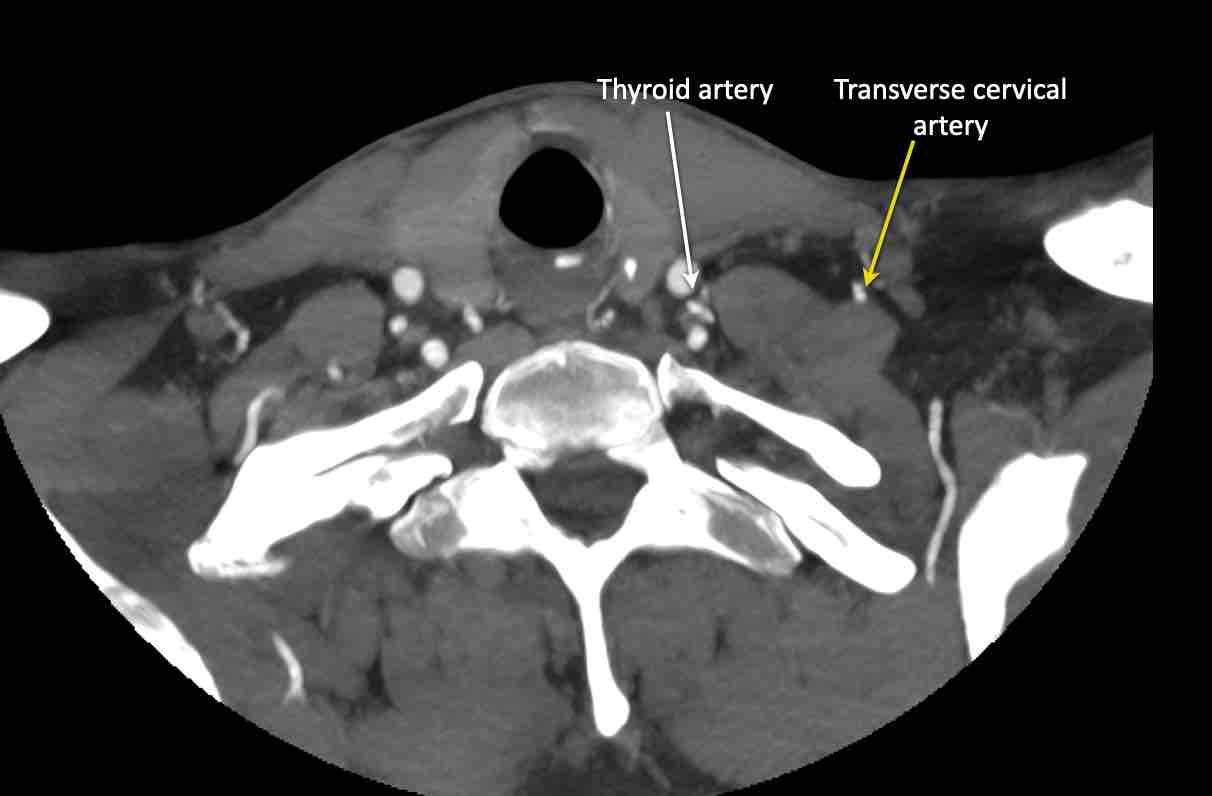

Động mạch cổ ngang

Cuộn qua các hình ảnh để xem giải phẫu của động mạch cổ ngang.